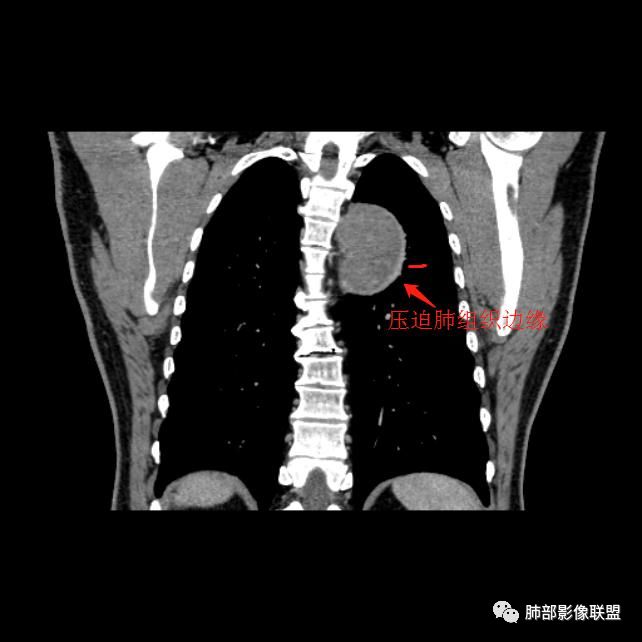

红日东升:左侧胸椎旁肿块,边缘清晰光整,冠状位见D字征,未见支气管进入,肺组织受压表现,定位肺外。轻度强化,密度稍不均匀,临近肋骨变细,未见肺动脉供血,考虑良性肿瘤,神经源性可能。右肺下叶病灶,轻度强化,血管显影,边缘平直、凹陷,考虑炎性病变。

张立:左侧胸椎旁肿块,边缘清晰光整,冠状位见D字征,未见支气管进入,肺组织受压表现,定位肺外。轻度强化,密度稍不均匀,,未见肺动脉供血,神经源性肿瘤,节细胞神经瘤可能。右肺下叶病灶,轻度强化,血管显影,边缘平直、凹陷,TB可能。

长沟流月去无声:中年男性,慢咳起病,左后纵隔可见一大占位,D字征,胸膜掀起,有胸膜尾征,附近肺组织受挤压,血管纹理纠集,瘤肺界面清晰,较均匀轻-中度强化,瘤肺表面可见线样不张之强化影,供血血管来源不易确定,冠状位似乎见一纵隔血管出入,综合考虑神经源性肿瘤:神经纤维瘤,神经鞘瘤?右下外斑片密度影,估计炎性,但本次手术应该未处理。

ZK金:定位:左肺下叶后综合脊柱旁肺外肿块,胸膜尾征,D字征,瘤肺交界面清晰,肺组织受压。影像表现:边界清晰,密度均匀,上下经线略横经。首先考虑神经源性肿瘤,神经节细胞瘤首选,鞘瘤和孤立性纤维瘤鉴别诊断。右肺下叶考虑炎症。

Shelia??:左下胸腔脊柱旁类圆形软组织肿块影,呈D字证,可见胸膜掀起,邻近肺组织受压呈弧形致密影改变,增强后似轻度均匀强化,邻近骨质未见明显异常,考虑良性病变,孤立性纤维瘤?鉴别神经源性肿瘤另外右肺小叶不规则病灶,边缘平直收缩为主,局部可见弓形凹陷,密度均匀,增强后轻中度均匀强化,周围肺野尚清晰,考虑炎性肉芽肿病变,OP?但是感觉周围太光整,还是就是慢性炎症?

田园晚风:左胸后部近胸椎占位,密度均匀,边缘光滑,呈d字征,外侧可见压缩肺组织,右肺见条状致密影,与支气管走行一致,考虑左侧神经源性肿瘤,右肺abpa?

1.左上胸内脊柱旁半圆形肿块,质地坚实,密度比较均匀。

2.病灶周边见胸膜掀起,应当考虑胸壁或是纵隔来源,肺内病变不会如此。

3.降主动脉这一相对固定结构向前方推移,提示病灶相对坚实且有牢固附着点,不支持来自柔软的肺组织。

综上,病灶定位胸壁或后纵隔,就发病率而言,神经源性可能性较大。